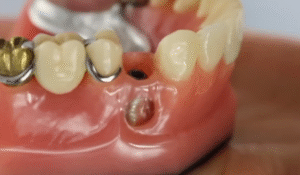

Cheapest Options for a Missing Tooth: Budget-Friendly Solutions That Actually Work

A missing tooth isn’t just a cosmetic issue—it affects how you eat, how you feel about yourself, and honestly, your wallet. Dental work can be...